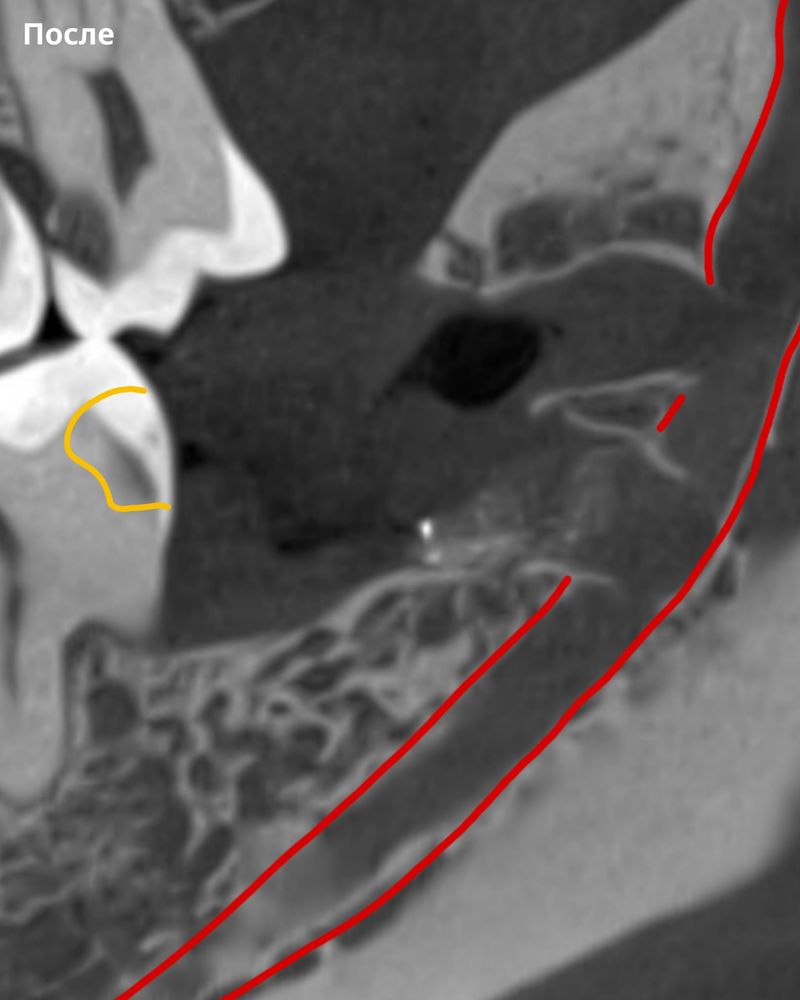

Сложный зуб мудрости и как мы его удалили без риска для нерва

Мы в Kandinsky Clinic умеем работать с такими сложными ситуациями. В нашей команде есть опытные неврологи, которые при необходимости могут восстановить чувствительность, но мы стараемся предотвратить любые осложнения сразу.

В этом случае операция прошла успешно и без осложнений для нерва, а пациент избавился от боли и проблем с зубами.